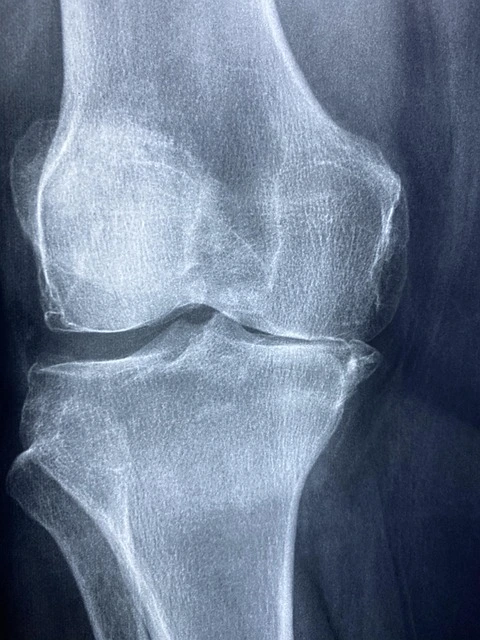

๋ฌด๋ฆ ํต์ฆ ์ฆ์, ์ฐ๊ณจ ์์์ ์ ํธ๋ฅผ ์์์ฐจ๋ฆฌ์

๋ฌด๋ฆ ์ฐ๊ณจ์ ํ ๋ฒ ์์๋๋ฉด ์์ฐ์ ์ผ๋ก ์ฌ์๋์ง ์๊ธฐ ๋๋ฌธ์ ์กฐ๊ธฐ ๋ฐ๊ฒฌ์ด ๋งค์ฐ ์ค์ํฉ๋๋ค. ๋ค์๊ณผ ๊ฐ์ ์ฆ์์ด ์๋ค๋ฉด ์ ๋ฐ ๊ฒ์ฌ๊ฐ ํ์ํฉ๋๋ค.

์ฐ๊ณจ ์์ ์ด๊ธฐ ์ฆ์

- ๋ฌด๋ฆ ์์ชฝ ๋๋ ๋ฐ๊นฅ์ชฝ ํต์ฆ (ํน์ ๋ฐฉํฅ์ผ๋ก ์์ง์ผ ๋ ์ ํ๋จ)

- ๊ณ๋จ ์ค๋ฅด๋ด๋ฆด ๋ ๋ป๋ปํ ๋๋

- ์ค๋ ์์ ์๋ค๊ฐ ์ผ์ด๋ ๋ ๋ฌด๋ฆ์ ์ฐ๋ฆฟํ ํต์ฆ

- ๋ฌด๋ฆ์์ ‘๋ฑ’ ์๋ฆฌ๊ฐ ๋๋ฉด์ ๋ถํธํจ

- ๋ฌด๋ฆ ๋ถ๊ธฐ๋ ์ด๊ฐ

์ด๋ฐ ์ฆ์๋ค์ด ์ง์๋๋ค๋ฉด, MRI ๋ฑ ์์ ๊ฒ์ฌ๋ฅผ ํตํด ์ ํํ ์์ ๋ถ์๋ฅผ ํ์ธํ๊ณ , ํ์์ ๋ฏธ์ธ์ฒ๊ณต์ ์ ๊ณ ๋ คํ ์ ์์ต๋๋ค.